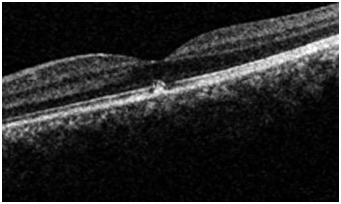

Figure 3 OCT right eye with no significant changes.

Figure 4 OCT left eye showing retinal pigment epithelial changes.

Fundus examination revealed retinal pigment epithelial changes on the fovea confirmed by OCT scan which is corresponding with the central scotoma on Amsler grid monitoring. Follow-up examinations revealed reduction in the area of RPE (retinal pigment epithelial hypertrophy) with no or little improvement of visual acuity measured by standardized Snellen or log MAR equivalent. There was no improvement in the area of central scotoma. The mystery remained on the power or class of laser pointer used. The RPE hypertrophy did not warrant any treatment as there was minimal evidence of inflammation and or fluid on the OCT scan. The RPE changes explained the area of scotoma and resolution in the thickness mapping of the subfoveal changes. After follow up of three months the patient who was a Turkish immigrant was lost to follow up (Figure 1–4).